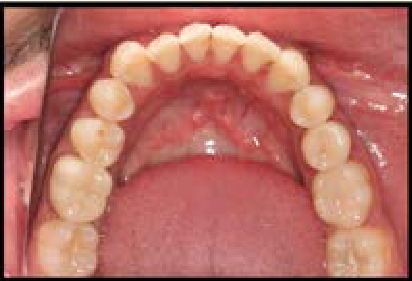

Khyati Arora, Lakshbir Singh, Navneet Kaur and Gurpreet Kaur. 21(12): 29-39.

Aylin Pasaoglu Bozkurt. 21(12): 50-58.